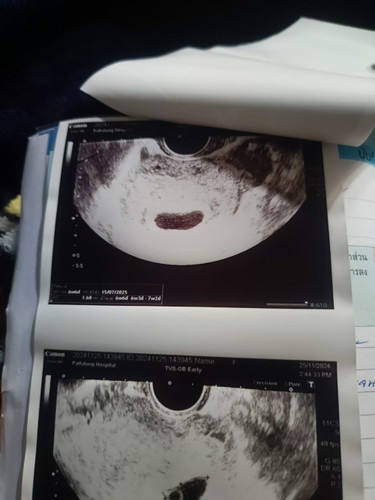

หมออัลตร้าซาวด์ 2 รอบ รอบที่ 1 ตอน 25/11 รอบที่ 2 วันที่ 2/12 ตามใบอัลตร้าซาวด์ใบที่ 1 และ 2 เลยค่ะ หมอบอกยังไม่เจอตัวน้อง และได้ระบุว่าท้องลม แม่ๆดูภาพแล้วคิดว่าแม่บ้านนี้ยังมีหวังว่าจะเจอตัวน้องอีกไหมคะ อายุครรภ์ยังไม่ชัดเจนเพราะประจำเดือนคลาดเคลื่อน แต่คาดเดาจากขนาดถุงตั้งครรภ์ตอนนี้น่าจะประมาณ 6 วีคค่ะ #ขอคำแนะนำกับแม่ๆด้วยนะคะ

ของเค้าหมอซาวตอน6-7วีคเหมือนกันเจอถุงตั้งครรภ์หมอบอกว่าไม่เจอตัวอาจจะท้องลม หมอจะให้ยากระตุ้นออกเพราะท้องลมเขาบอกแต่เรายังไม่อยากเชื่อเลยรอไปอีก9วีคไปซาวอีกคลีนิคเจอตัวน้องพร้อมหัวใจเลย แม่ใจเย็นนะน้องยังเล็กอย่าคิดมากค่ะ ตอนนี้เขาได้26วีคแร้วถ้าเชื่อหมอปานี้คงไม่ได้อุ้มท้องแร้วเพราะเขาว่าท้องลมให้กินยาเอาออก

อ่านเพิ่มเติมใจเย็นๆค่ะแม่ เพราะอายุครรภ์ยังไม่ชัดเจน แต่ดูแล้วมีถุงไข่แดงอยู่นะค่ะ เราก็ไปฝากตอน6wเหมือนกันเจอแต่ถุงตั้งครรภ์กับถุงไข่แดง หมอนัด 9wไปตรวจ เจอตัวน้องแล้วหัวใจน้องแล้วค่ะ คุณแม่ใจเย็นๆ ไม่ต้องเครียดน้าา เดียวน้องก็มา

เหมือนเห็นก้อนกลมในถุงการตั้งครรภ์นะค่ะภาพถัดไปจากภาพแรก บางทีไข่ตกช้าแม่รองรอไปก่อนซักระยะค่ะเผื่อน้องยังเล็ก